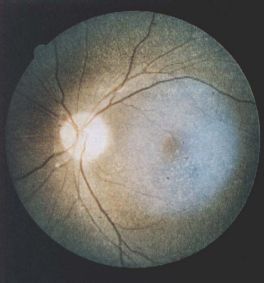

Fine, yellow refractile deposits throughout the retinal layers in cystinosis[32]- Infantile nephropathic cystinosis is the most common (95%) and severe presenting within the first year of life with failure to thrive, growth retardation and renal tubular acidosis leading to renal failure within the first decade of life.

- The first sign of cystinosis is cystine deposits in the cornea and conjunctiva during the first year of life resulting in symptoms of photophobia and blepharospasm.[27][34][33][35][36] The infantile nephropathic cystinosis is the only from having fine, yellow refractile deposits throughout all the retinal layers, RPE and choroid, especially in the periphery of the posterior pole.[3] Diffuse RPE mottling is the most common posterior segment finding that results in a golden-brownish reflex.[37] Pigmentary retinopathy, when present, precedes the appearance of the corneal crystals and can be observed as early as 5 weeks of age.[35][38] With age the retina can display bone spicule pigment migration that resembles retinitis pigmentosa. Progressive retinal degeneration causes decreased visual acuity, constricted visual fields, and decreased cone-rode function.[35] Simultaneously, when photophobia manifests patients with infantile nephropathic cystinosis will have fluid and electrolyte loss, aminoaciduria, glucosuria, phosphaturia, hypercalciuria and hypochloremic acidosis. These patients can present with growth retardation and hypothyroidism.[7]